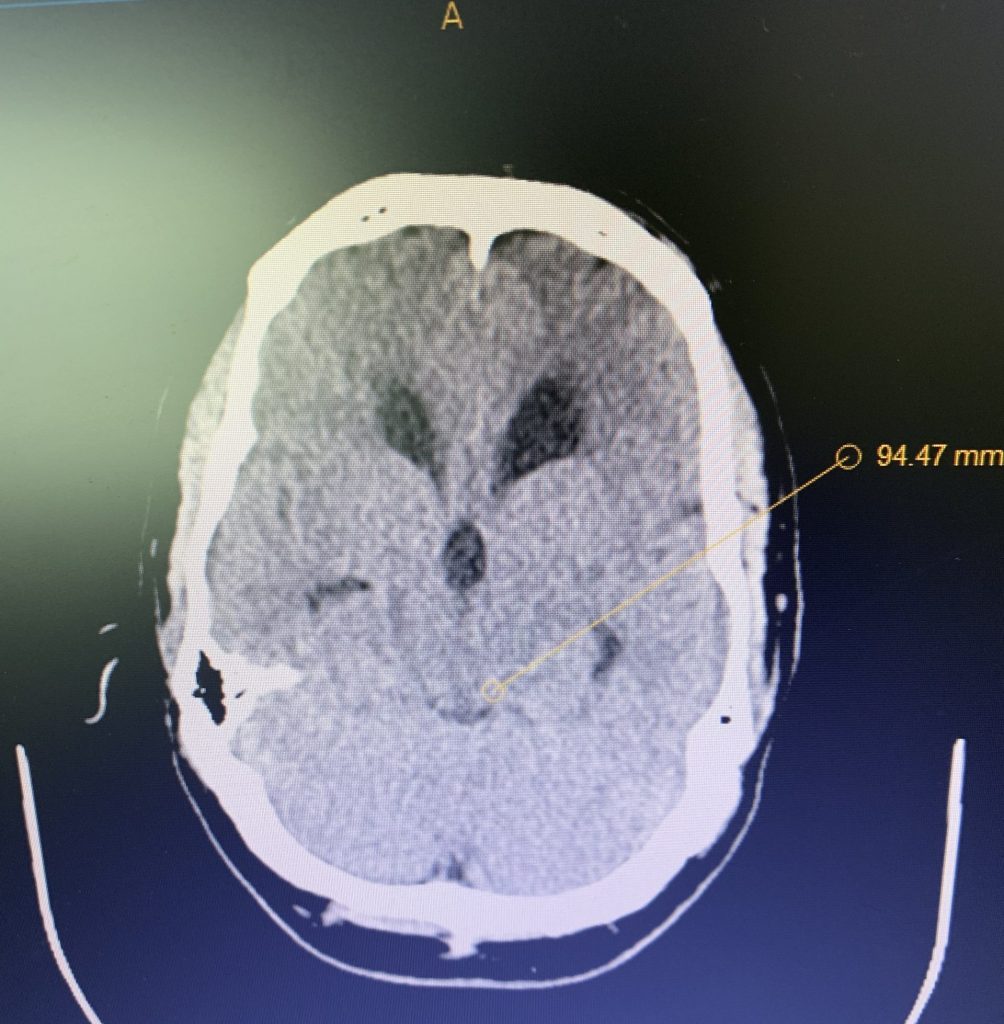

Brain:

Cerebellar Hemangioblastoma

Author: Michael Brisman M.D., F.A.C.S., Read More!